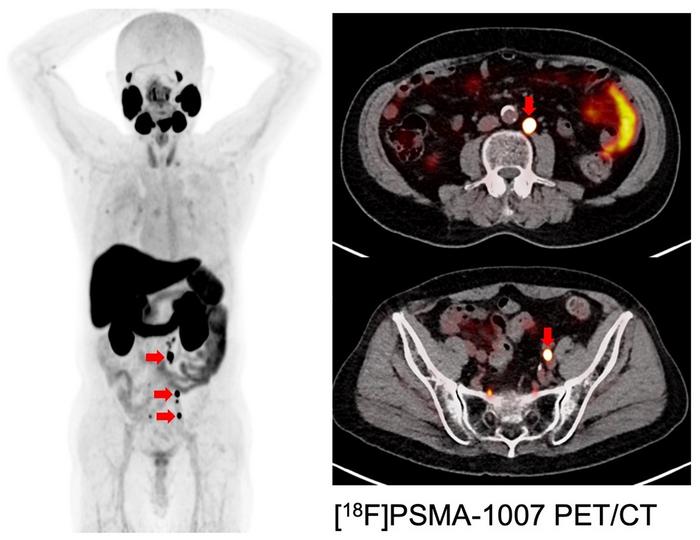

In recent years, theranostics, which involves changing the radionuclide labeled to a compound that binds to a target, has been attracting attention as an integrated approach from cancer diagnostic imaging to therapy. Prostate-Specific Membrane Antigen (PSMA) is also gaining recognition as an innovative target for theranostics, enabling deployment from PET (positron emission tomography)-imaging based lesion detection to targeted radionuclide therapy. Furthermore, alpha irradiation from inside the body via intravenous injection enables treatment of metastases throughout the body.